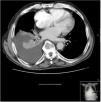

Chest CT scan revealed right free-flowing pleural effusion 5 cm thick, causing passive atelectasis of the right lower lobe (Fig. 1), with no other changes.